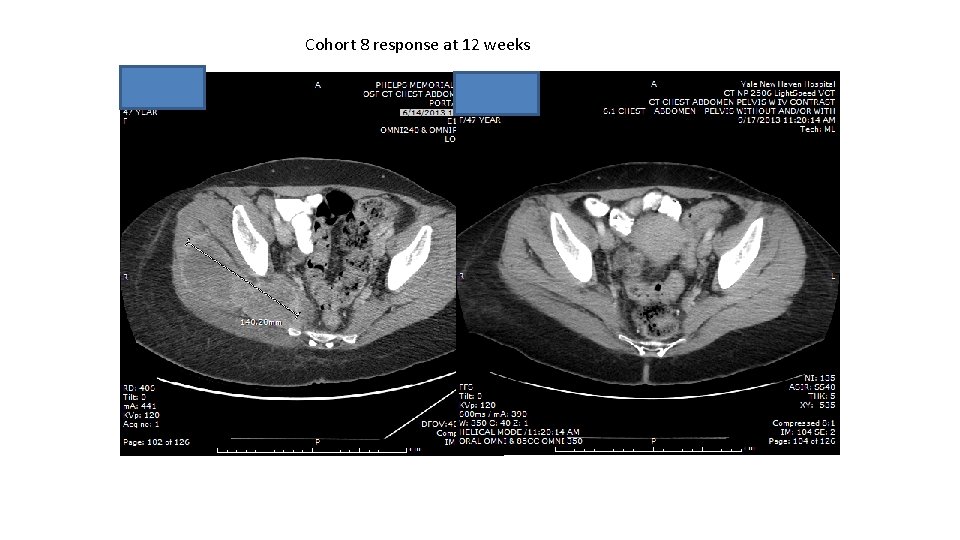

Cohort 8 response at 12 weeks